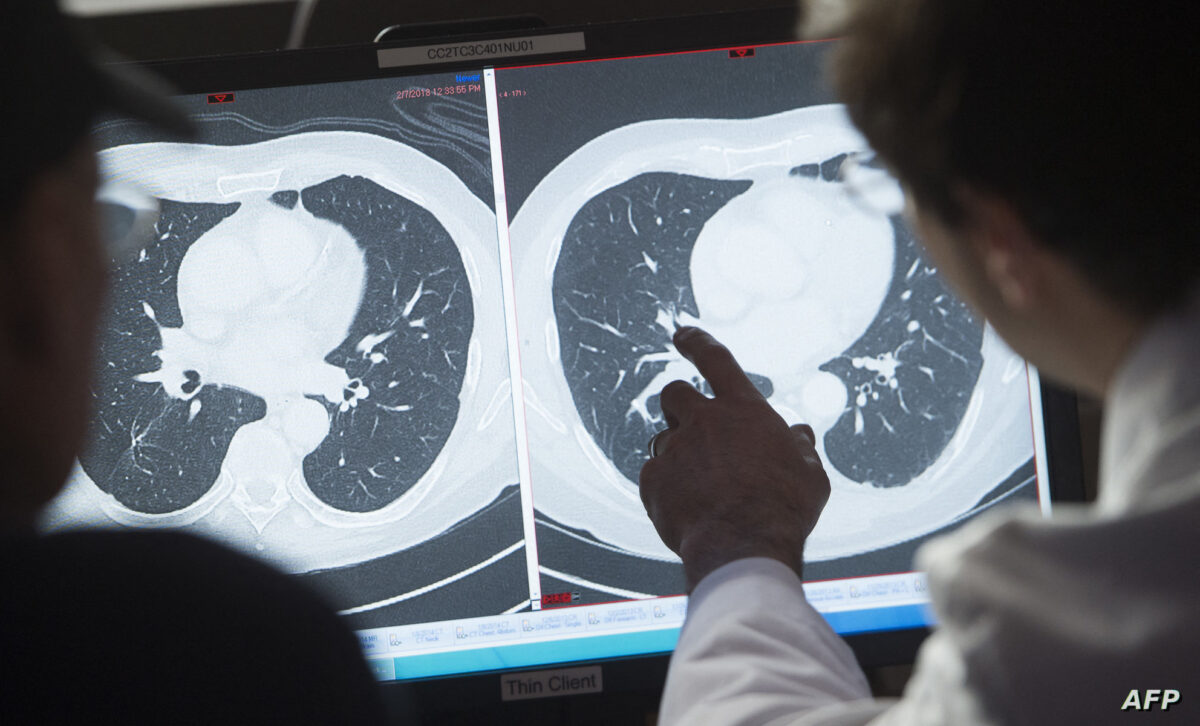

وفحص الباحثون قواعد بيانات صحية وطنية في الولايات المتحدة لا سيما بين المصابين بمرض السرطان، ووجدوا أن التدخين هو العامل الأساسي المسبب لهذا المرض بفارق كبير، حيث تصل نسبة المصابين بهذا المرض بين المدخنين 20 في المائة.

وذكر أعضاء بفريق الدراسة، في تصريحات نقلها الموقع الإلكتروني «هيلث داي» المتخصص في الأبحاث الطبية أنه «رغم التراجع الكبير في عدد المدخنين، فإن عدد حالات الإصابة بسرطان الرئة في الولايات المتحدة المرتبطة بتدخين السجائر يثير القلق».

وعند فحص أنواع السرطان المختلفة، اتضح للباحثين أن 100 في المائة من سرطان عنق الرحم و90 في المائة من سرطان الرئة و80 في المائة من سرطان الجلد تقع بسبب عوامل يمكن للإنسان تلافيها عن طريق تغيير نمط الحياة الذي يخوضه.